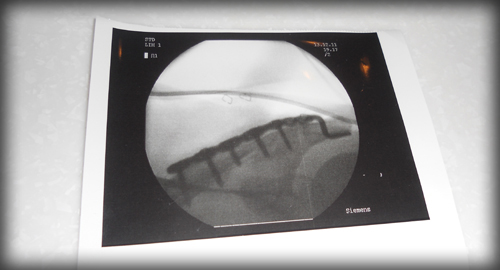

※左鎖骨をボルト六ヶ所と金具で改造人間となりました

2011年12月13日(午前8時8分くらい)自宅より職場へ出発し1.5km先で

横断歩道のない片側一車線づつの広い幹線道路をBianchiInfinitoで走行中に道路を渡った推定50代サラリーマンと接触事故を起こしました(´・ω・`)

2012年1月1日、事故による鎖骨骨折とボルト手術より3週間目ですが日に日に痛みも和らぎ腕は上がらないものの肩の可動域も広がり復帰ライドとして葛西臨海公園公園まで久しぶりに走ってきました。